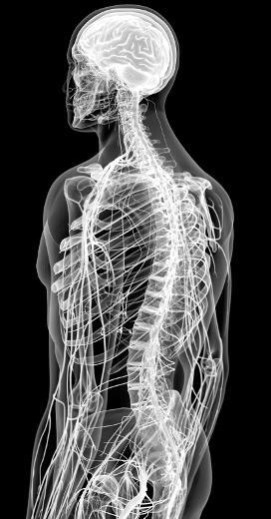

Наш спинной мозг отлично поживает внутри костей спины.

Соединить центральную нервную систему с остальной частью организма достаточно сложно. Здесь, как и в системе кровообращения, нужна крупная сеть специальных структур, разветвляющихся в каждый сантиметр тела. ПНС делает это с помощью 43 пар нервов.

31 пара спинномозговых нервов служит переносчиком как сенсорных, так и моторных сигналов. Эти нервы иннервируют соматические и вегетативные отделы ПНС в областях ниже шеи. Некоторые нервы объединяются, образуя нервную сеть под названием «сплетение». Начиная со второго поясничного нерва и до самого конца позвоночника спинномозговые нервы свободно плавают в СМЖ, образуя пряди, похожие на конский хвост. Их так и называют – конский хвост.

Периферические нервы выходят из спинного мозга.